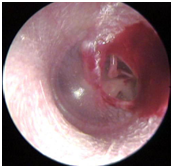

Ear wax impactions- Although the “Q” in Q-tips originally stood for “quality” I do not think it was in reference to getting a quality ear cleaning. In fact, there are few things that do a poorer job of cleaning the ear than Q-tips. You likely formed the habit of using q-tips to remove wax from the ears. In reality, the Q-tip only pushes the wax deeper into the ear canal making it harder to remove and facilitating the formation of a wax impacted ear canal. If your doctor informs you that you have an impacted ear canal, it means that the ear canal is completely (or almost completely) blocked with earwax. (See picture 1)

Picture 1- picture of ear wax in the ear canal. The ear drum is seen behind the ear wax. |